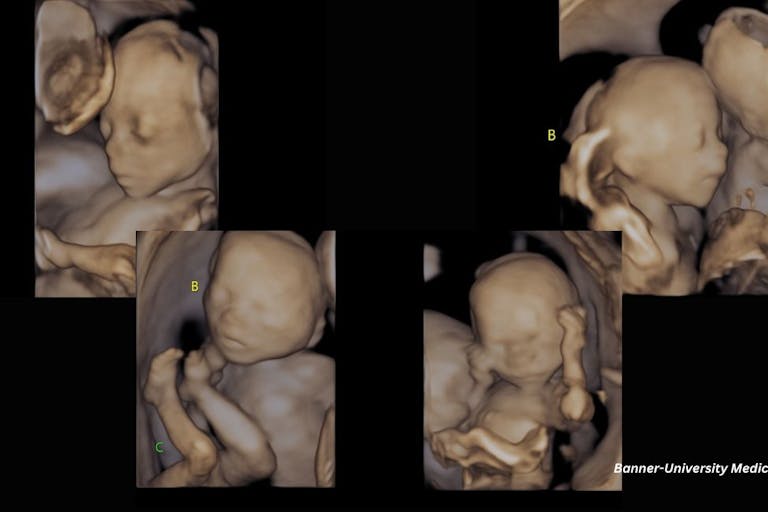

Rachel and Marco Vargas recently welcomed spontaneously conceived identical quadruplets — a miracle that only happens in about one in 40 million births, according to their doctor.

The Rhode Island couple’s journey began in 2024 when they discovered they were expecting quadruplets — all identical girls. While they celebrated the pregnancy as a miraculous blessing, it also came with significant medical risks.

Two of the girls were diagnosed with twin-to-twin transfusion syndrome, or TTS, a dangerous condition where uneven blood flow between twins can result in one twin receiving too much blood, while the other receives too little. In addition, one of the babies was diagnosed with a congenital malformation. Throughout the pregnancy, Rachel and Marco faced the heart-wrenching uncertainty that every parent dreads: whether all of their daughters would survive.

Seeking specialized care, they turned to the Twin to Twin Transfusion Syndrome Foundation, which connected them with Dr. John Elliott, a globally recognized expert in high-order multiple pregnancies at Valley Perinatal Services in Phoenix, Arizona. Dr. Elliott helped navigate the complex medical challenges of carrying quadruplets. Without hesitation, the couple relocated to Phoenix when Rachel was 21 weeks pregnant, and by 23 weeks, she was admitted to Banner University Medical Center for pre-term labor.

On January 24, at 30 weeks, Rachel gave birth to four healthy girls via cesarean section. Sofía, Philomena, Veronica, and Isabel each weighed around three pounds—much larger and healthier than expected.